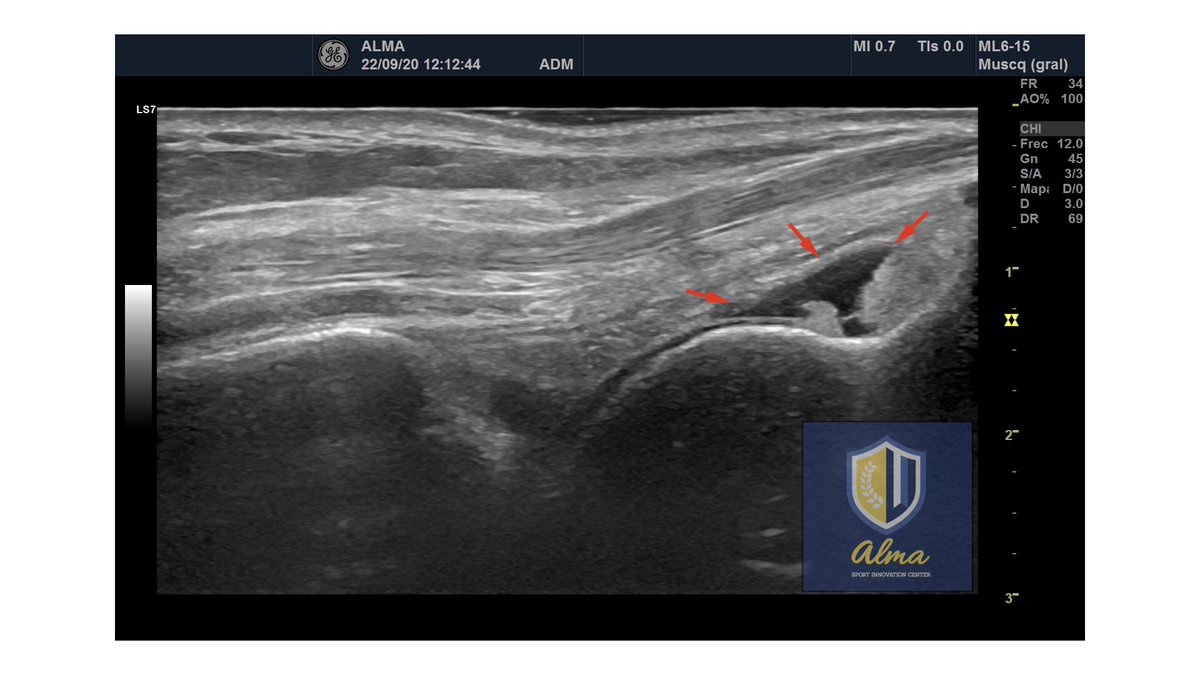

La #fisioterapiainvasiva, siempre #ecoguiada para aplicarla con la máxima eficacia y seguridad. 🔵#Endomed182E para #electrólisispercutánea de Enraf-Nonius Nederland ➕ 🔵Ecógrafo #LogiqV2 de @GEHealthcare Llévate este pack y disfruta de nuestros descuentos en #fisiotecnología